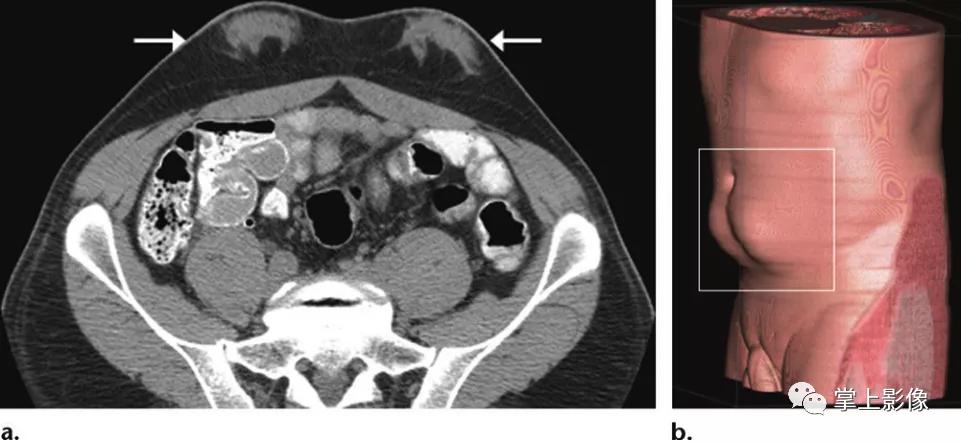

42岁男性胰岛素依赖型糖尿病患者胰腺移植后胰岛素注射部位的脂肪肥厚。脐下轴位CT(A)和斜矢状位最大密度投影CT(B)显示两侧对称的脐下肿块状突起(a为箭头,b为方形)。这些胰岛素注射部位双侧皮下脂肪肥大,并伴有中央浸润性软组织衰减。这些是胰岛素注射部位腹壁脂肪肥大的表现